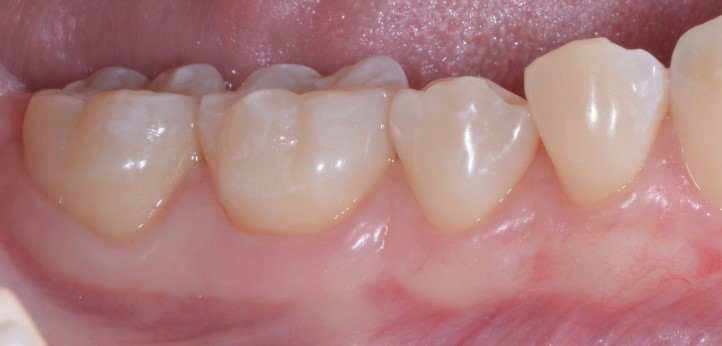

Cosa vedi di strano nella foto qui sotto? Ti sembra che la gengiva di Francesca abbia dei problemi?

Io direi proprio di no e sicuramente tu non puoi che concordare con me. Una bella gengiva rosa e sana.

C’è un trucchetto di mezzo però. Devo confessarti che ho usato Photoshop, ma non per cambiare lo stato di salute dei tessuti (non saprei neanche come fare in verità!!) guarda qui cos’ho fatto…

Ho semplicemente cancellato via i punti di sutura. Sì perché quello è proprio l’aspetto della guarigione a 10 giorni di un lembo a spostamento coronale multiplo con innesto di connettivo prelevato dal palato! Concorderai con me che è un intervento abbastanza “aggressivo”. Si deve scollare un lembo a spessore misto, sezionale le fibre muscolari, spostare coronalmente il lembo, prendere un pezzo di “gengiva” dal palato (qui di solito i pazienti rabbrividiscono) e ficcarla sotto il lembo.

Vediamo il caso iniziale. Francesca presentava recessioni multiple con accentuata ipersensibilità dentinale.

Perché, secondo te, Francesca ha accettato di farsi tagliuzzare in 2 punti per risolvere questo problema? Te lo spiego io: perché io sapevo di poterle dare questa guarigione a 10 giorni

e questa a sei mesi.